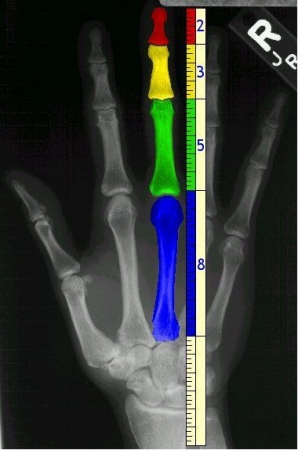

হাতের আঙ্গুলের হাড়ের দৈর্ঘ্যে সোনালী অনুপাত এবং ফিবোনাচ্চি নাম্বার দেখা যায়, এই ছবির মত:

এবার আমাদের আছে ২ হাত, প্রতি হাতে ৫ আঙ্গুল, ৮ আঙ্গুলে ৩ ভাগ করে, ১ আঙ্গুলে ২ ভাগ। এগুলো সব ফিবোনাচ্চি সংখ্যা!!